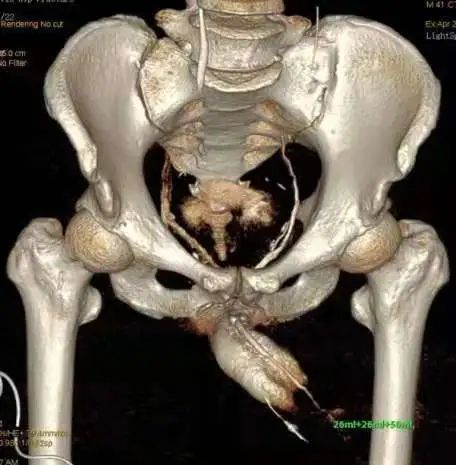

3.海绵体CT三维重建

V检查时间短,摄片次数少,减轻经济负担

V检查者避免了X线辐射

V三维重建图像清晰,分辨率高,可显示.部分静脉漏的部位、 勃起后有无侧弯畸形、海绵体充盈缺损等

V不能动态显示,不能测压